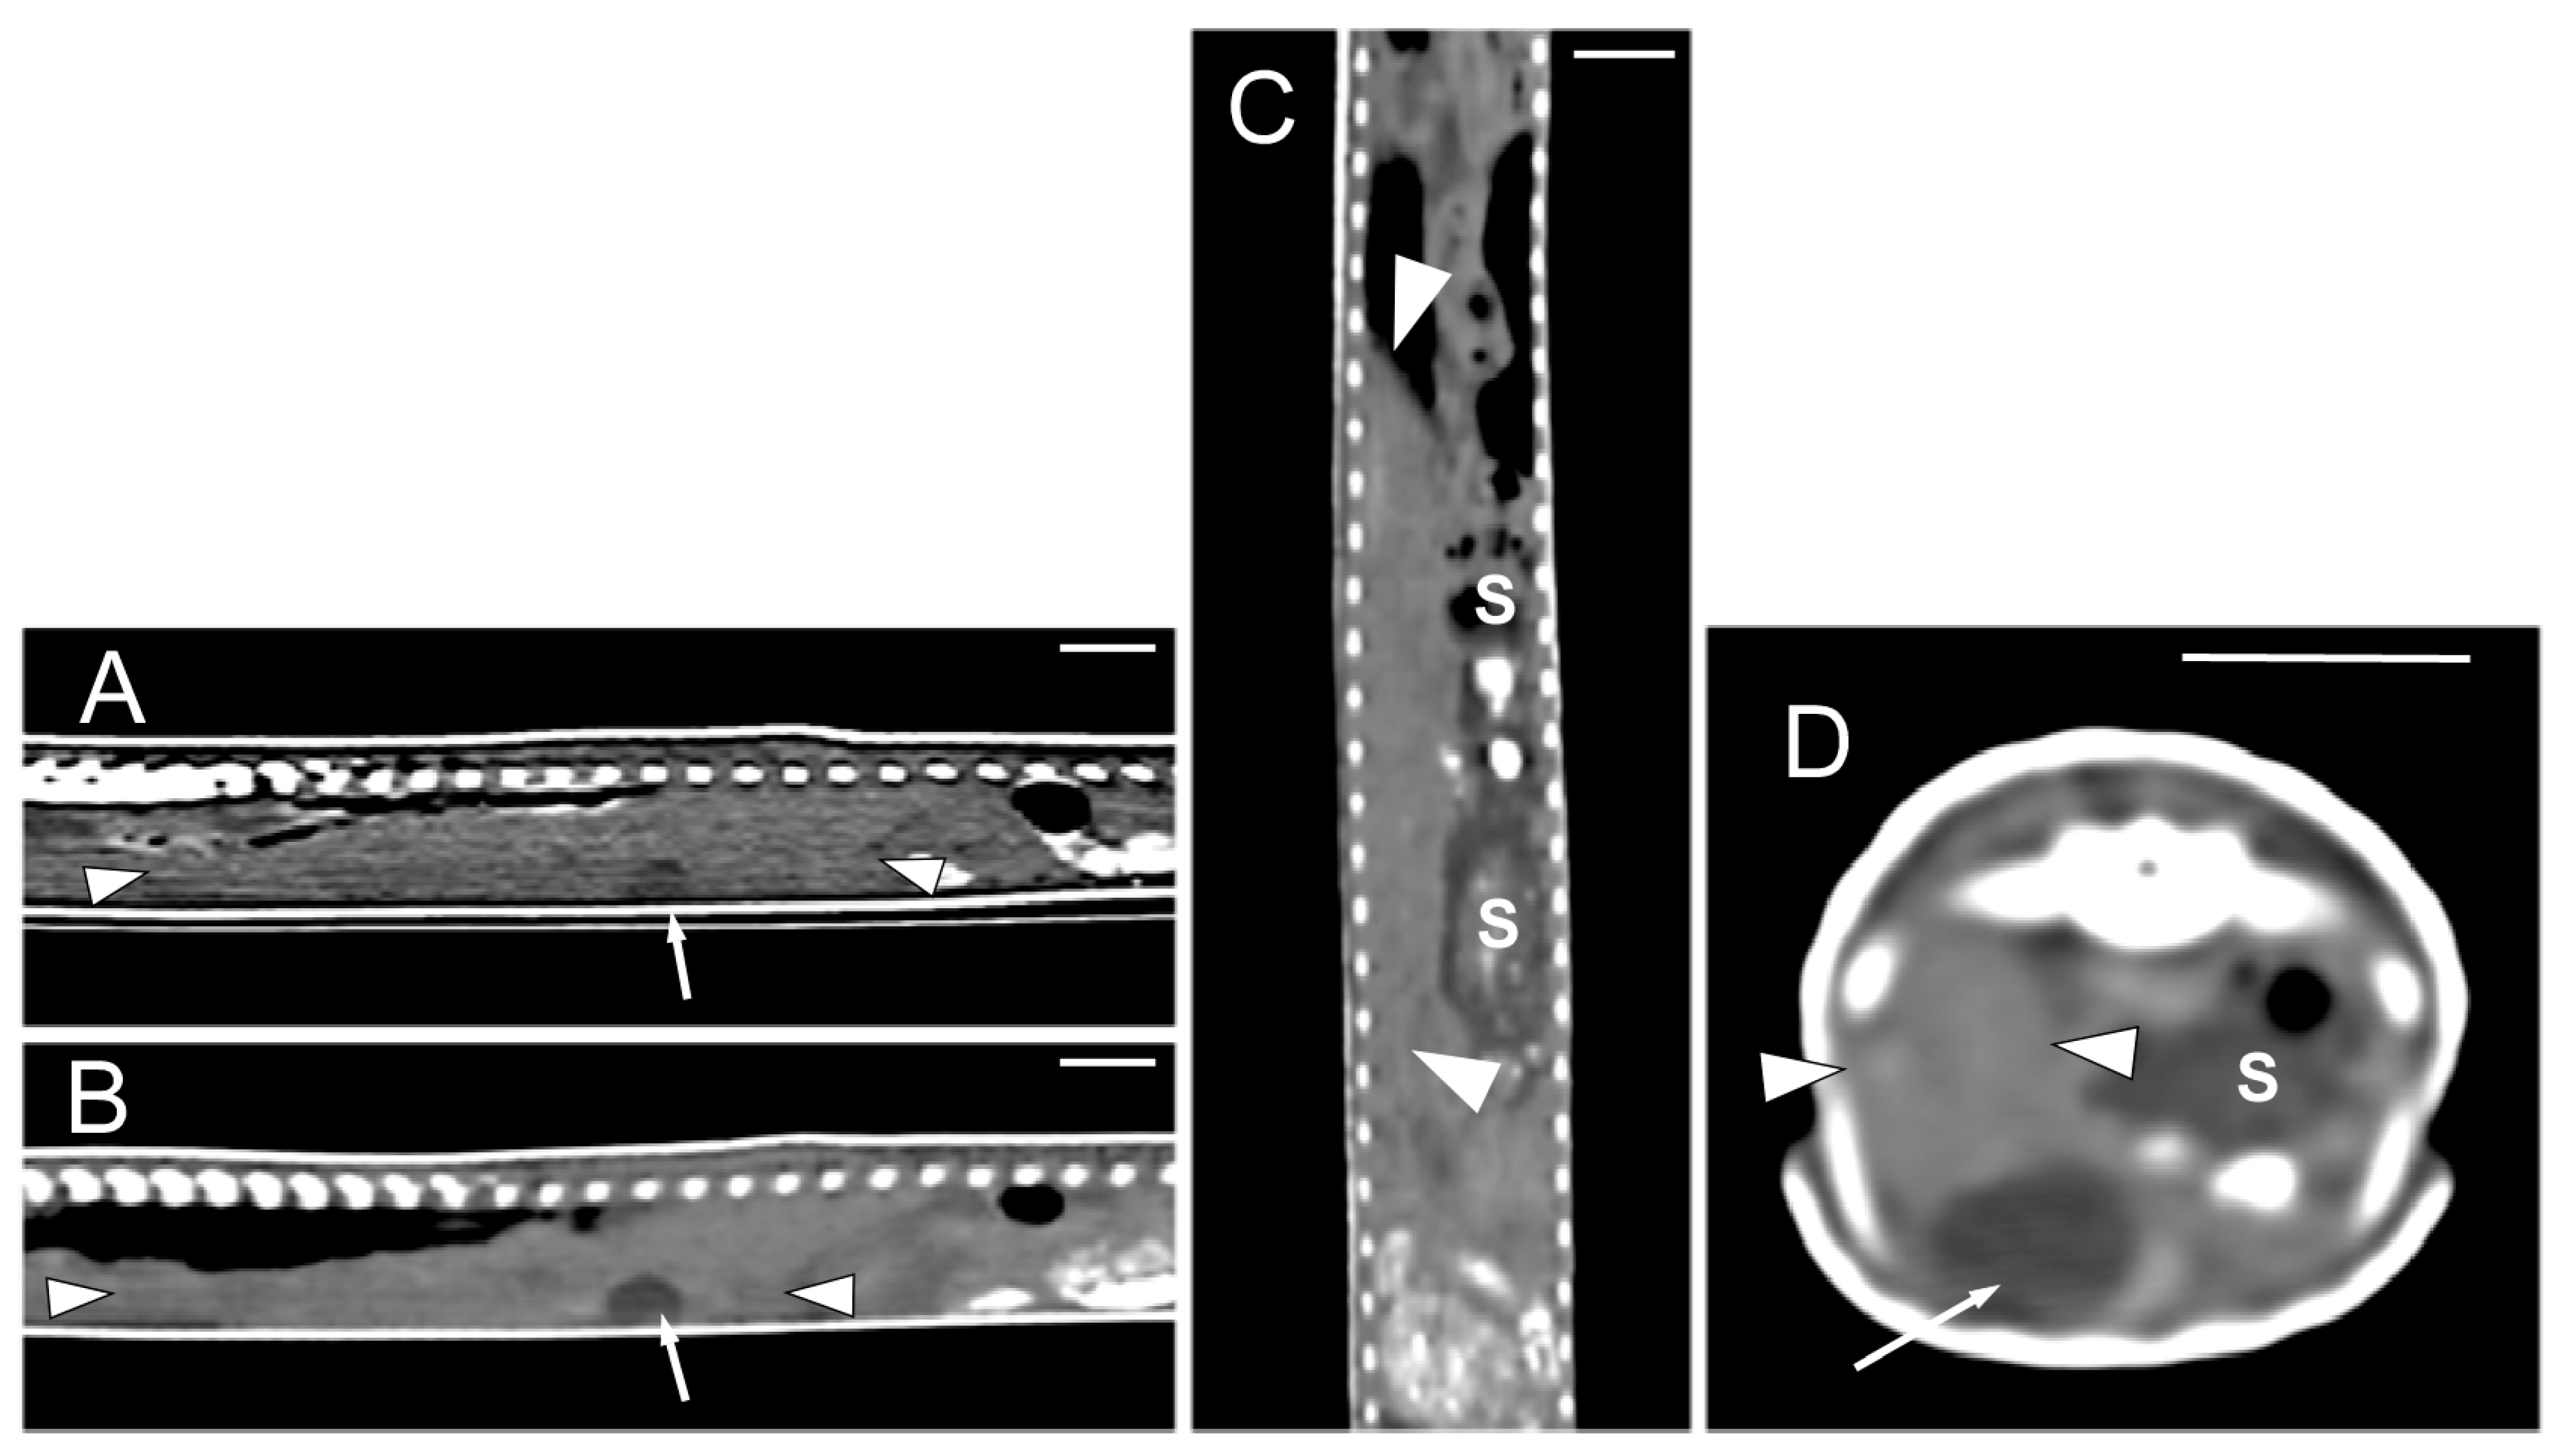

The morphology of the hyoid bone was most clearly observed in the dorsal plane, in the CT images obtained from the MPR reconstruction (Figure 6A). The trachea was clearly distinguished as a tubular structure containing gas in the lumen, extending from the glottis to the main bronchial bifurcation; the sagittal plane allowed the visualization of its entire length (Figure 6B). The heart and some great vessels were best identified in postcontrast images (Figure 6C–F). The dorsal and sagittal planes were the most suitable for observing the slight distinction between the atria and the ventricle of the heart (Figure 6C,D). On the contrary, the sinus venosus, the two cranial cava veins, and the aortic arches were most clearly observed in the dorsal plane (Figure 6D,E). The aorta was identified along the midline, just ventral to the spine, and was best observed in the sagittal plane (Figure 6F). The pulmonary trunk, divided into the left and the right pulmonary arteries, and the thyroid gland, were not identified in the CT images.

Figure 6.

The CT images of Pseudopus apodus in the dorsal (A,D,E) and sagittal (B,C,F) planes showing the hyoid bone (A), the trachea (B), the atria and ventricle (C,D), the sinus venosus and the two cranial cava veins (D), the aortic arches (E), and the dorsal aorta. The images (C–F) were obtained after contrast media administration. See the list for abbreviations. Bar = 10 mm.